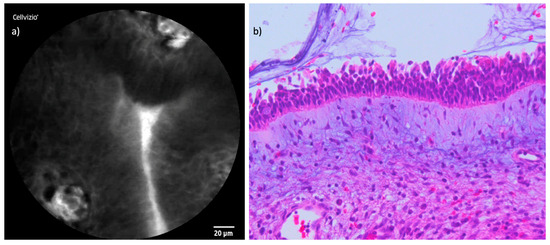

3.1. Healthy Mucosa

The examination of the healthy mucosa surrounding the tumors revealed uniform and characteristic features. In terms of cellular configuration, the healthy mucosa exhibited a regular, oval to polygonal architecture with clearly defined borders. Capillaries appeared small, with a round to oval shape, and were individually distinguishable without any evidence of perivascular fluorescein leakage. The uptake of fluorescein was homogeneously distributed throughout the healthy tissue, providing a uniform contrast that allowed clear visualization of cellular and vascular structures. Figure 3 and Figure 4 demonstrate the CLE findings of healthy mucosa and respiratory epithelium compared to corresponding histopathological cross-sections.

Figure 3. Juxtaposition of CLE and histopathological cross-section in healthy mucosa: (a) CLE image of endonasal mucosa of the inferior turbinate; (b) regular endonasal squamous epithelium with hematoxylin and eosin (H&E) staining.

Figure 4. Comparison of CLE and histopathological cross-section respiratory epithelium: (a) CLE image of the endonasal respiratory epithelium of the nasal septum with cross-sections of capillaries. (b) Corresponding respiratory epithelium, also with cross-sections of capillaries in hematoxylin and eosin (H&E).